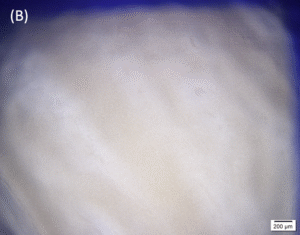

Photos of the Petri plates, 72 hours after bacterial (Pseudomonas aeruginosa) inoculation.

Image (A) shows positive bacterial growth inhibition (full translucency) at the treatment site after one dose of

UV-C for 15 seconds at 10 mm distance.

Image (B) is the control plate. The blue lines divide the plate into quadrants.